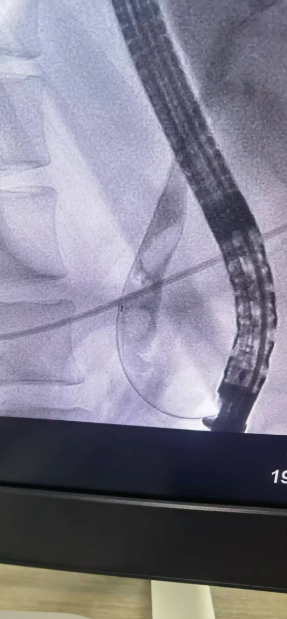

· 巧妙取石: 造影顯示,患者膽總管下端有3顆直徑約1.5cm的嵌頓性結石。專家采用球囊擴張、網(wǎng)籃取石等一系列高精尖技術,成功將結石完整取出,瞬間,淤積的膽汁順利引流通暢。

· 鼻膽管引流: 為充分引流、控制感染,術中順利放置了鼻膽引流管。整個手術流程如行云流水,僅用時不到半小時的時間便宣告成功?;颊?/span>生命體征平穩(wěn),梗阻即刻解除。